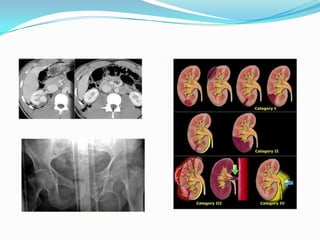

Triage- òðèàæ  ßàðàëòàéàìü òýíññýí ¿åèéí, àìü íàñàíä àþóëòàé ãýìòýëòýé ÿàðàëòàé ýðчèìò ýìчèëãýý øààðäëàãàòàé ºâ òºí  ßàðàëòàé ýìчèëãýýã 1-2 öàã õ¿ëýýæ áîëîõ ãýìòýëòýé ºâчòºí  Õàìãèéí õºíãºí, ýñâýë àìáóëàòîðèéí ýìчèëãýýíä ýìчèëãýýã ¿ðãýëæë¿¿ëæ áîëîõ ãýìòýëòýé ºâчòºí  Íàñ áàðñàí, ýñâýë àìü íàñ àâðàõ áîëîìæ áàéõã¿é ãýìòýëòýé ºâчòºí

ßàðàëòàé òóñëàìæèéí ýðýìáëýíÿëãàëòûí ¿íäñýí ¿éë àæèëëàãàà  Èðñýí ¿éëчë¿¿ëýãчèéã ýìч áà ñóâèëàãч õ¿ëýýí àâч ò¿¿íèé áèåèéí áàéäàë, àìèí ¿ç¿¿ëýëò, ýìíýëç¿éí øèíæ òýìäã¿¿äèéã ¿íäýñëýæ äàðààõ 4 ýðýìáý áóþó çýðýãëýëýýð ýðýìáýëýí ÿëãàíà.  Ýðýìáý 1: Àìü íàñ ýðñäýõ, àìèí ýðõòýíèé ¿éë àæèëëàãàà çîãñîõ àþóë øóóä çàíàëõèéëñýí, ñýõýýí àìüäðóóëàõ õîéøëóóëàõøã¿é òóñëàìæèéã 2-5 ìèíóòûí äîòîð ¿ç¿¿ëæ ýõëýõ øààðäëàãàòàé òîõèîëäëóóä õàìààðàõ áºãººä óëààí ºíãèéí ïàéç ç¿¿æ ÿëãàíà.

Ýðýìáý-2 áóþó õî¸ðäóãààðçýðýãëýëä àìèí ýðõòýíèé ¿éë àæèëëàãàà íîöòîé àëäàãäñàí, àìü íàñ ýðñäýõ ºíäºð ìàãàäëàëòàé ýìíýëãèéí ÿàðàëòàé áîëîí ýðчèìò ýìчèëãýýã 10 ìèíóòûí äîòîð ¿ç¿¿ëæ ýõëýõ øààðäëàãàòàé òîõèîëäëóóä õàìðàíà. Øàð ºíãèéí ïàéç ç¿¿æ ÿëãàíà. Óã ýðýìáýä õàìðàõ ýìíýë ç¿éí õàì øèíæ¿¿ä

Ýðýìáý -3 ãóðàâäóãààðçýðýãëýëä àëü íýã ýðõòýí ñèñòåìèéí ýýíýãøèë àëäàãäààã¿é, ýìíýëãèéí òóñëàìæ ¿éëчèëãýýã 30 ìèíóòààñ 1 öàã õ¿ðòýë õóãàöààãààð õ¿ëýýõ áîëîëöîîòîé òîõèîëäëóóäûã õàìðóóëàõ áà ýíý á¿ëãèéí ¿éëчë¿¿ëýãчèä íîãîîí ºíãèéí ïàéç ç¿¿æ ÿëãàíà.

Ýðýìáý -4 áóþóäºðºâä¿ãýýð çýðýãëýëä ¿éëчл¿¿ëýãчèéí ýðõòýí ñèñòåìèéí ¿éë àæèëëàãààíû ¿ç¿¿ëýëòýíä àðõàã áîëîí ÿëèìã¿é ººðчëºëò èëýðñýí, ÿàðàëòàé òóñëàìæ øààðäëàãàã¿é, ýìíýëãèéí òóñëàìæ ¿éëчèëãýýã 1-2 öàãèéí õóãàöààãààð õ¿ëýýõ áîëîìæòîé, çºâõºí ýìíýëãèéí ¿çëýã çºâëºãºº øààðäëàãàòàé òîõèîëäëóóäûã õàìðóóëàí, ¿éëчл¿¿ëýãчèä öàãààí ºíãèéí ïàéç ç¿¿æ ÿëãàíà.